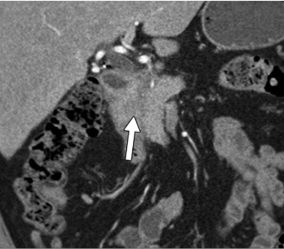

- A. Circumferential irregular submucosal wall thickening noted in D2 and D3 segment of duodenum causing luminal narrowing.

- B. Few hypoenhancing areas within the medial wall of duodenum. Uncinate process of pancreas appears oedematous.

- C. Contrast is seen passing from the duodenum into the jejunum. No contrast leakage noted.